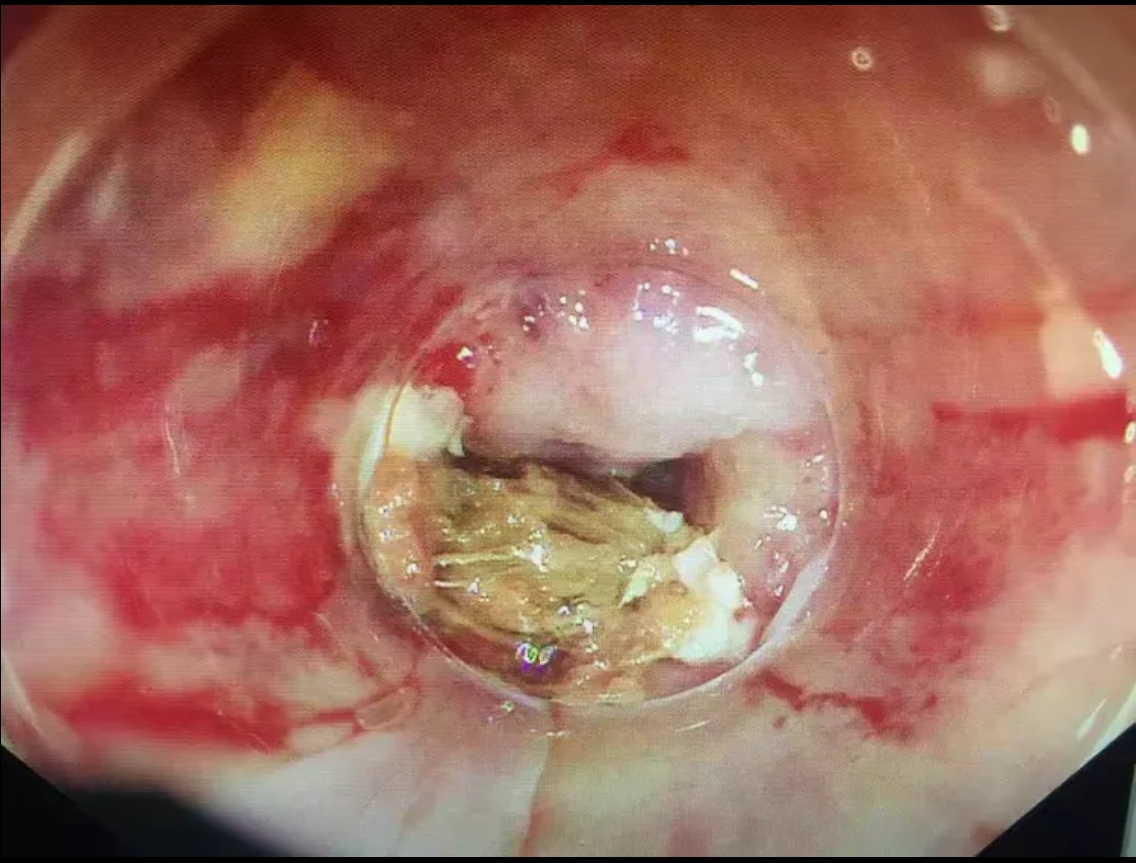

第二步:立即就醫(yī)內(nèi)鏡中心是首選??捎秒娮游哥R直觀地發(fā)現(xiàn)并取出食道的異物。

特別警告:紐扣電池是“頭號(hào)殺手”!如果懷疑兒童吞食了紐扣電池,必須爭分奪秒送往醫(yī)院。電池會(huì)在濕潤的食道內(nèi)泄漏強(qiáng)堿性物質(zhì),短短幾小時(shí)內(nèi)就能造成食道嚴(yán)重?zé)齻?、穿孔,后果不堪設(shè)想。